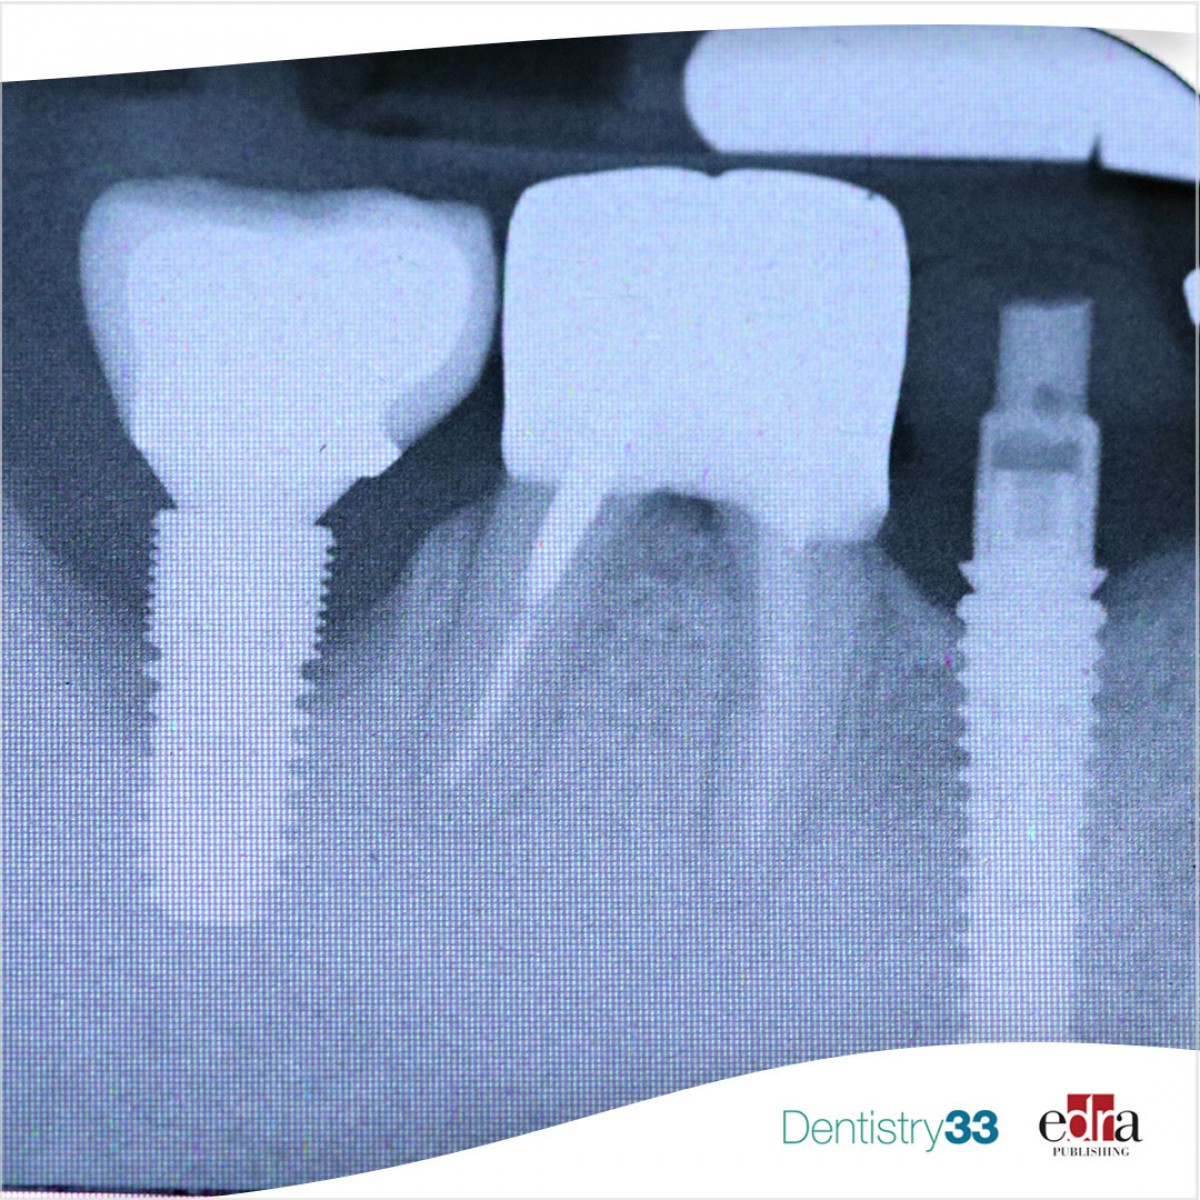

Smoking also increases the risk of both early and late implant failure and is associated with more postoperative infections and peri-implant marginal bone loss.

However, despite this topic having been debated for years, the evidence for smoking as a risk factor for peri-implantitis still remains inconclusive.

From the data of this review, it can be concluded that smoking is associated with peri-implantitis at both the patient and implant level.

Peri-implantitis is associated with bacterial plaque biofilms and with patients who have a history of periodontitis. Smoking is a risk factor for periodontitis, but the relationship between smoking...